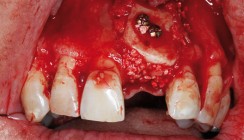

Implantation

Nach Entfernung des Osteosynthesematerials konnten drei Monate später die restlichen Implantate (XiVE) in Lokalanästhesie (Articain 4 % mit 1 : 100.000 Adrenalin: Ultracain D-S forte, Sanofi-Aventis, Frankfurt am Main) und Sedierung (Midazolam, 5 mg/5 ml) unter perioperativer, antibiotischer Abschirmung (Penicillin G, 1 x 106 IU, einmalige Gabe) komplikationslos inseriert werden (Abb. 20). Hierbei zeigte sich ein rötliches, d.h. von vielen Blutgefäßen durchwachsenes und somit sehr gut regeneriertes Transplant (Abb. 19 und 20).